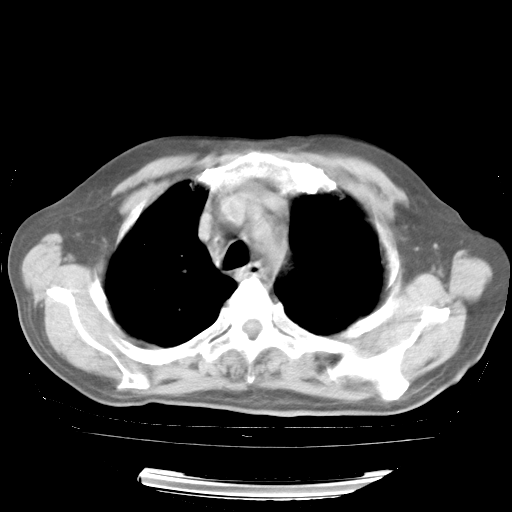

4月28日肺部CT——再次出现类似去年5月9日——透光度降低,“间质性”改变。

4月28日肺部CT——再次出现类似去年5月9日——磨玻璃样、间有“粟粒样”改变。

4月28日肺部CT